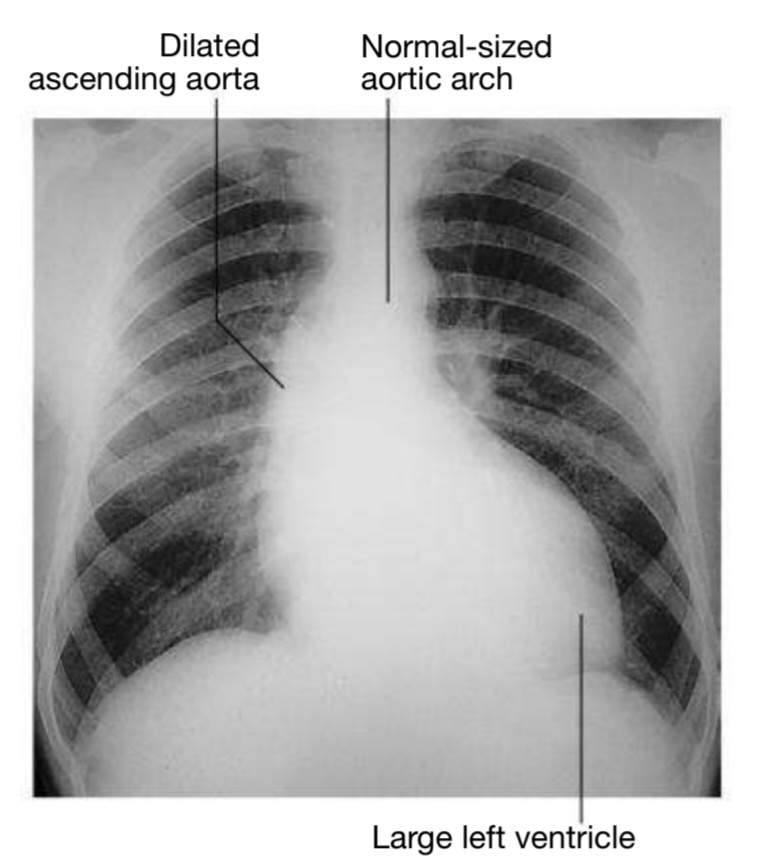

X-ray

X-Ray Imaging Table of Contents X-ray imaging is a diagnostic medical procedure used in various clinical conditions such as fracture,.......